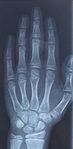

Hệ thống xương

Hai bàn tay của con người có tổng cộng 27 xương: cổ tay bao gồm 8 xương, lòng bàn tay có 5 xương, và 14 xương còn lại là các xương của ngón tay (bao gồm cả ngón cái).

8 xương của cổ tay được sắp xếp thành hai hàng, mỗi hàng gồm 4 xương. Những xương này liên kết chặt vào một cấu trúc xương không sâu hơn được hình thành bởi các xương cẳng tay.

Lòng bàn tay có 5 xương được gọi là xương lòng bàn tay, mỗi xương của một ngón tay. Mỗi xương lòng bàn tay có đầu, trục và chân.

Con người có tổng cộng 14 xương trong ngón tay, còn được gọi là các đốt ngón tay hay đốt xương ngón tay. Có 2 xương ở hai ngón tay cái (ngón tay cái không có đốt xương giữa - đốt xương màu xanh dương trong hình), và 3 xương ở mỗi ngón tay còn lại.